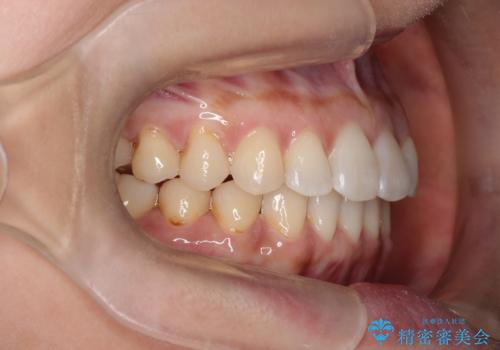

前歯のがたつきと隙間の矯正 インビザラインにて

- 上顎の前歯のがたつきと、下の前歯の隙間を主訴に来院されました。

下の前歯が先天的に欠損していました。

上顎の歯と歯の間をわずかに削りスペースを作り、ガタガタの改善し、下顎の前歯は隙間を閉じる計画としました。

非常に協力的な患者様でしたので、早期に治療が終了することができました。